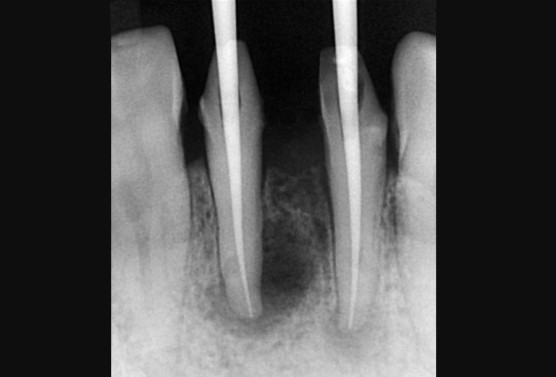

[MTA 이용한 신경치료 마무리]

뿌리 끝에 약재가 펌핑되어서 나온모양이 보이나요?

제일 이상적으로 신경치료가 마무리 되었을 때 나오는 형상이죠.